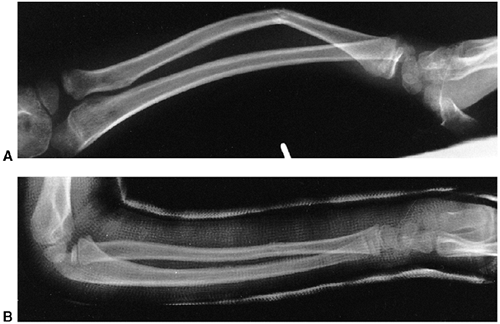

Several classification systems have been proposed since Foucher first

described different types of physeal fractures in 1863 (30). The most widely used classification of physeal fractures is that described by Salter and Harris (31). There are five types of fractures in this classification. Rang has added a sixth that is commonly recognized (Fig. 33.2) (32).

Figure 33.2 Salter-Harris classification. A: Type I is a transepiphyseal separation without evidence of a metaphyseal fragment. B:

In type II, the fracture line is through the physis, exiting into the metaphysis, leaving a small triangular portion attached to the physeal plate (i.e., Thurston Holland fragment). C: The type III fracture is an intraarticular fracture, with the fracture traversing the physis and exiting through the epiphysis. D: Type IV describes a vertical fracture line that is intraarticular. It passes through the epiphysis, physis, and metaphysis. E: Type V fracture describes a crush injury to the physis that usually is not apparent on initial injury films. F: Type VI fracture is a localized injury to a portion of the perichondrial ring. Subsequent healing produces bone formation across the perimeter of the physis, connecting the metaphysis to the epiphysis. |